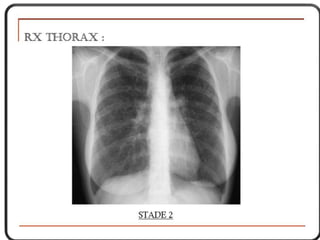

a) radiographie du thorax

La “masse”= aspect d’une opacité de forme, de dimension

et de siège très variable dans médiastin

On précisera

- le type : unique ou multiple, rond,

bossé ou polycyclique

- le siège: compartiment du médiastin

- l’homogénéité ou l’hétérogénéité de

l’opacité.(calcifications)

Opacité médiastinale

- homogène

- limite externe nette

- continue,

- convexe vers le poumon,

- se raccordant en pente douce

- avec le médiastin

- à limite interne

- Invisible(noyée ds le médiastin)